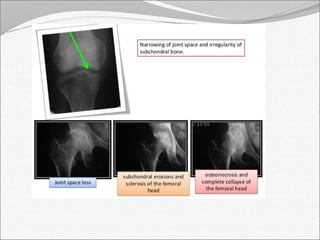

X-RAY:

 Early stage –soft tissue swelling, loss of tissue planes,

widening of joint space and slight sublaxation due to

fluid in the joint.

 Late stage – narrowing and irregularity of joint space

 Periosteal reaction, bone destruction and

sequestrum formation

Joint space

decreased

osteophytes AP view

Imaging: X-RAY: Early stage –soft tissue swelling, loss of tissue planes, widening of joint space and slight sublaxation due to fluid in the joint.  Gas may be seen with E.coli infection  Late stage – narrowing and irregularity of joint space  Periosteal reaction, bone destruction and sequestrum formation

Joint space decreased osteophytes AP view